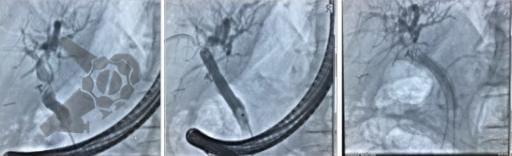

L.R.S., masculino, 8 meses, nascido a termo, com diagnóstico pré-natal de atresia de esôfago com fístula traqueoesofágica distal (Vogt IIIb/Gross C), submetido à correção cirúrgica no 3º dia de vida. Aos 3 meses, passou a apresentar episódios recorrentes de tosse durante a alimentação, engasgos, regurgitação e perda de peso progressiva. A mãe relatou dificuldade em introduzir alimentos sólidos e episódios recorrentes de infecção respiratória nos últimos dois meses. Solicitada endoscopia digestiva alta, que evidenciou estenose puntiforme da anastomose esofágica. Iniciada terapia endoscópica com dilatação esofágica utilizando vela de Savary-Gilliard. Foram realizadas 4 sessões com intervalo de 2 semanas, com melhora progressiva da aceitação alimentar e ganho ponderal adequado. Após a 4ª dilatação, o paciente encontra-se em boa evolução clínica, com alimentação por via oral plena, sem episódios de engasgos ou perda ponderal.

O tratamento inicial a ser considerado é a dilatação endoscópica, seja com o balão hidrostático ou com a vela de Savary – Gilliard, não havendo diferença nos desfechos, de acordo com a literatura atual, entre as duas técnicas [12]. Entretanto, alguns trabalhos sugerem que a dilatação com balão pode apresentar menor risco de complicações[12,13,14]. Estudos mostram uma média de três sessões de dilatação para a resolução do quadro, sendo estas intervaladas em um período de duas a quatro semanas, a depender da sintomatologia e evolução clínica do paciente, sendo o ganho ponderal um dos fatores clínicos mais importantes a serem considerados [8,13].